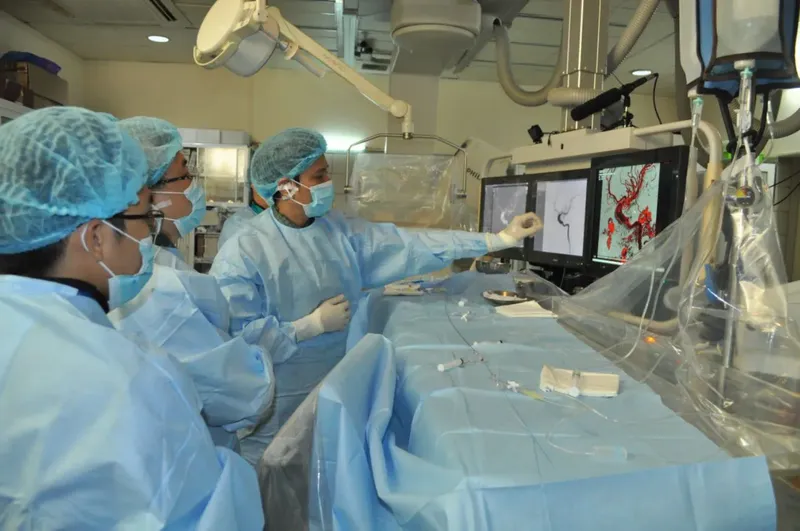

Anh Đức Hiếu – bệnh nhân ung thư đại tràng giai đoạn cuối tiếp nhận phương pháp giảm đau bằng điện quang can thiệp tại phòng khám đa khoa Hương Sơn, sau khi liên tiếp bị hành hạ bởi những cơn đau, mà các phương pháp giảm đau bình thường không đáp ứng.

Điện quang can thiệp trong giảm đau ung thư là một phương pháp mà bác sĩ sẽ sử dụng những thiết bị nhỏ (như kim tiêm, ống dẫn) để bơm thuốc giảm đau trực tiếp vào vị trí chính xác nơi có các dây thần kinh hay đám rối dẫn truyền cảm giác đau , bằng sự hỗ trợ của các phương tiện chẩn đoán hình ảnh như siêu âm, cắt lớp vi tính hoặc màn tăng sáng .

Ưu điểm của phương pháp này là không gây mê, không mất máu, thời gian tiến hành nhanh và hiệu quả thường có ngay sau thủ thuật – điều này là cần thiết, bởi các bệnh nhân ung thư giai đoạn cuối, tình trạng sức khỏe kém, suy kiệt khó có thể tiếp nhận các can thiệp lớn.